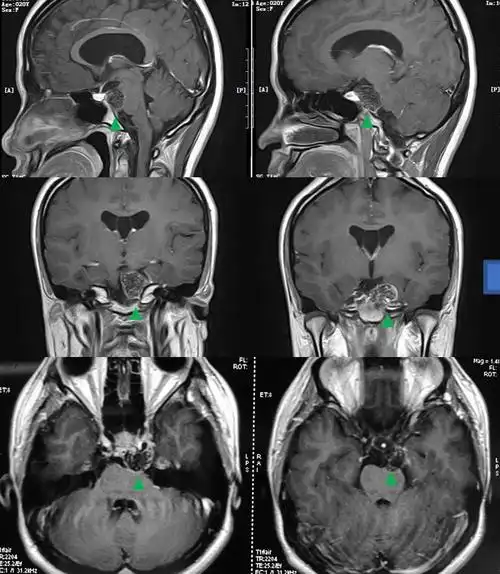

垂体瘤微创手术治疗之经鼻手术_垂体瘤_垂体瘤治疗方式 - 好大夫在线